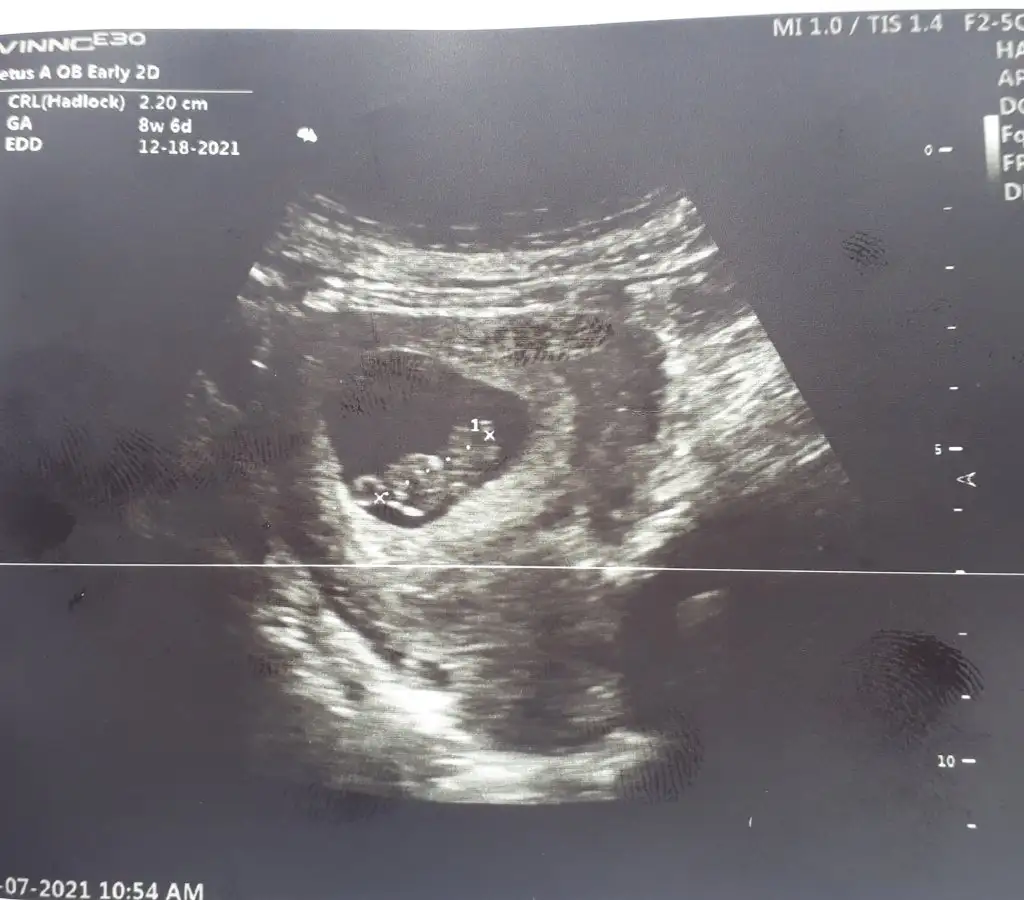

Ramzi teorisi okudum yüzde 97 dogruymuş.Ama neye göre bakcam ultrasona bilemedim. Size sormak istedim Bebeğim sağa daha yakın sanki bası da solda ayakları sağa bakıyor yani. Anlamadım ben. Sağlıklı olsun tabi kız erkek fark etmez ama merak ettim. İlk foto 5+5 iken 2.foto 9+3ken

Tabiki 7 8 haftalik ultrason kagidi varsa at alttan mi ustten mi soyle tahmin yapayim canimBanada bakarmısınız acaba rica etsem

Kiz gibi canim

Tam emin degilim kuzum ama bir dahaki ultrasonuda atarsin yine bakarizYaa teşekkür ederim inşallah hayırlısı ❤